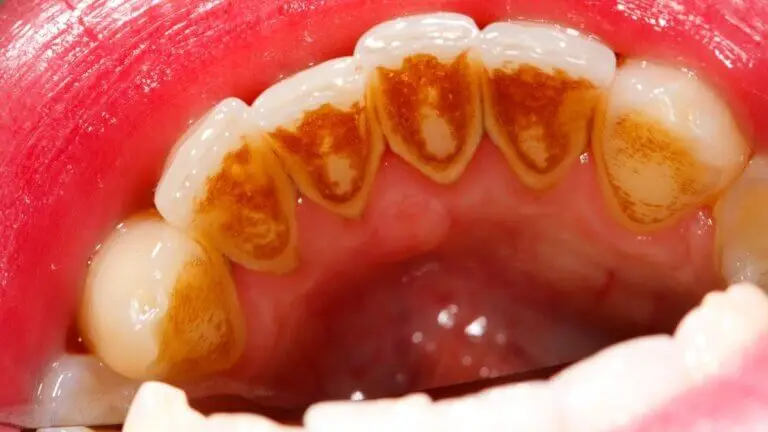

El sarro también conocido como «tártaro» o «cálculo dental», consiste en el endurecimiento de la placa bacteriana sobre la superficie de los dientes, casi siempre debido a una higiene oral deficiente.

Esta suciedad se puede apreciar debajo de la línea de las encías, sobre los dientes y en los empastes u otros trabajos dentales. Si no se remueve de forma adecuada, puede inflamar las encías, provocar mal aliento y conducir a trastornos más graves como las caries y la enfermedad periodontal.

En su estado inicial, suele presentarse con un color amarillento o blanquecino, pero cuando se forma debajo de las encías, el sarro puede volverse marrón, verde o negro. Esto no solo afecta la estética, sino también la salud bucal, en general.